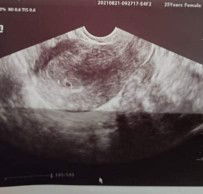

At least 4 weeks pregnant no embryo seen gestational sac palang

Hi ask ko lang kung may katulad kong case LMP is July 13 Positive pregnancy test Aug 17 1st Trans V Aug 21 due to frequent pain sa puson. Base sa tvs ko hindi sya sakto sa 5 weeks and 4 days yung image daw is at least 4 weeks plang and sac palang. May possibility po ba mag develop pa si baby? Mag wait daw ako at least 3 weeks para sa next tvs. Then meron din ba dto na nagkaron ng corpus luteum cyst while preggy. Malaki kase yung akin then last tvs ko last year wala naman sya. Worried lang kase ako first baby ko sana to. #1stimemom #firstbaby #pleasehelp #advicepls